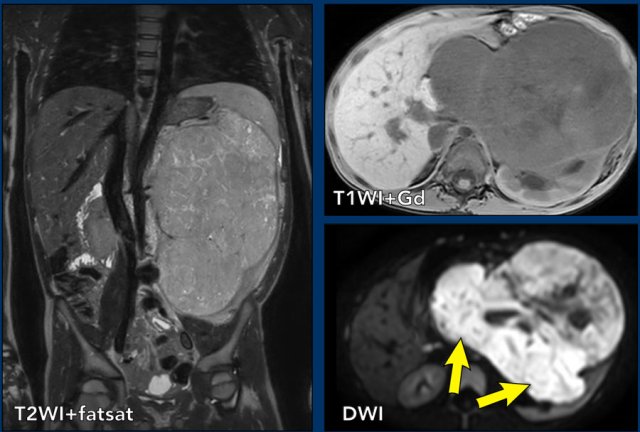

Nephroblastoma in a five-year-old boy. Nephroblastoma in a five-year-old boy.

More than 90% of renal tumors in children are Wilms tumors, also called nephroblastomas. Wilms tumor presents mostly in children between 6 month and nine years of age with a peak incidence from 2 to 3 years.

The coronal T2W-image shows an inhomogeneous tumor in the left kidney with small cystic components.

The tumor enhances less than the peripheral remnant of normal renal tissue.

The solid parts of the tumor show strong diffusion restriction (arrows).

This was a Wilms tumor in a five-year-old boy. Pre-operative chemotherapy was given according to the Umbrella protocol of the SIOP-RTSG after which a nephrectomy was performed.

Wilms tumors are mostly inhomogeneous, with decreased signal intensity on T1 and increased signal intensity on T2.

Necrotic cystic parts are often present.

Enhancement after Gadolinium is inhomogeneous and less than the enhancement of normal renal parenchyma.

The solid parts of the tumor will show restricted diffusion.

Signs of hemorrhage are often present. Hemorrhagic areas will also show restricted diffusion, so look at the T1 for signs of bleeding.